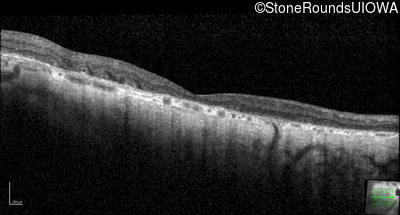

Optical Coherence Tomography - Right - 20/100 +1

Exemplar / OCT Stack